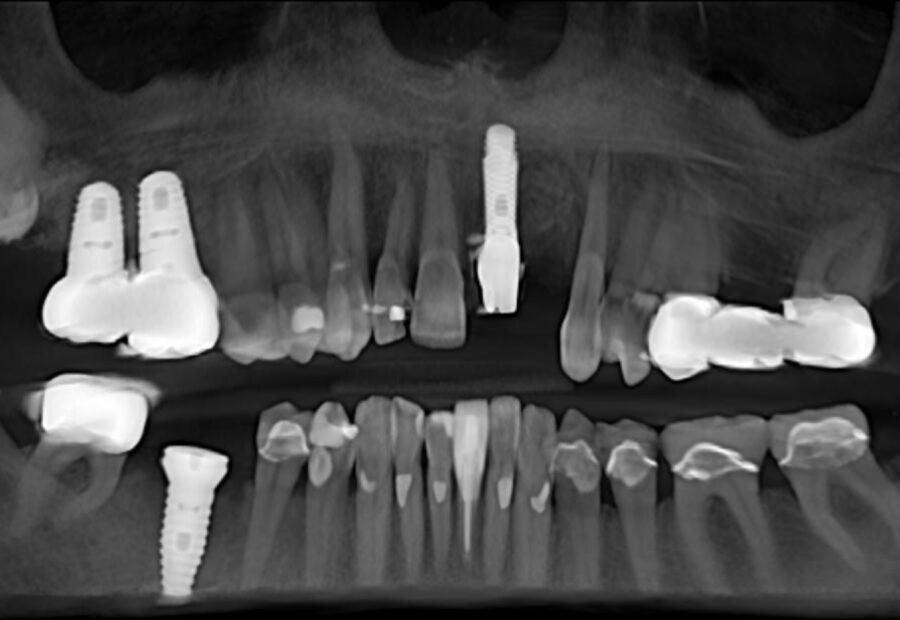

Experience the artful design and precision dentistry techniques that create masterful transformations. Our commitment to exceptional treatments begins with careful and customized planning, ensuring each patient receives tailored care of the highest quality. Discover how cutting-edge technology enhances every aspect of the dental experience, from diagnostics to treatment, delivering unmatched results and personalized comfort. Join us on a journey of dental excellence, where innovative practices and compassionate care combine to enhance smiles with exceptional results.